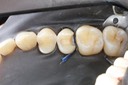

Kyle Chock #14 pre-op